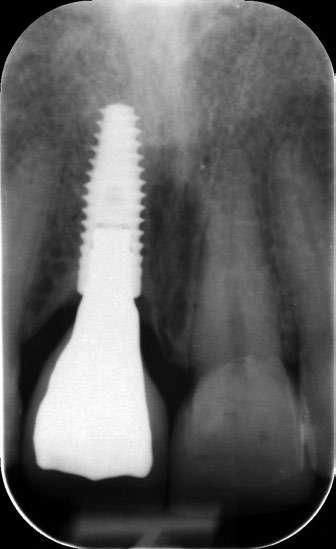

na paciente de 35 años (Figura 1) fue remitida a la Clínica de Odontología Reconstructiva de la Universidad de Zúrich debido a una infección crónica en el diente 11 y con expectativas estéticas muy altas. El diente 11 había sufrido un trauma hace 10 años y había sido tratado con multiple endodoncias sin éxito. El diente presentaba un absceso bucal (Figura 2), una bolsa periodontal aislado de 9 mm, y una ausencia de la tabla vestibular ósea (Figura 3). El diagnóstico se estableció como una fractura radicular vertical, lo que resultó en un pronóstico pobre. El plan de tratamiento consistió en una extracción combinada con preservación alveolar, colocación de implante diferido con injerto de tejido conectivo, una corona cerámica implantosoportada en 11 y una nueva carilla de cerámica para el diente 21.

El diente 11 fue extraído (Figura 4), seguido por la preservación alveolar. Se realizó un injerto pediculado de espesor parcial rotado del paladar (Figura 5), junto con una membrana de colágeno reabsorbible, un xeno-injerto bovino y cianoacrilato sellando al alveolo (Figura 6). La provisionalización consistió en un puente adhesivo de resina con dos alas de metal. El alveolo se dejó cicatrizar durante 6 meses, después de los cuales se tomó una impresión digital así como un escáner CBCT (Figura 7). Se llevó

a cabo una planificación digital para una cirugía guiada de implante en una posición protéticamente ideal (Figura 8). El implante 11 se colocó completamente guiado a través de una férula (Figura 9). Las dimensiones del reborde alveolar eran ideales para la colocación del implante en una posición atornillada (Figura 10), al igual que la calidad del hueso cicatrizado. Un injerto de tejido conectivo subepitelial fue estabilizado ocluso-bucalmente al implante (Figura 11) y el puente adhesivo fue recementado (Figura 12). Después de 3 meses de cicatrización, se realizó una restauración provisional y se acondicionó adecuadamente para dar forma al perfil de emergencia, imitando el del diente adyacente (Figura 13). Después de una fase provisional, se tomó una impresión analógica individualizada para el implante 11 y el diente 21 (Figura 14). El laboratorio fabricó una corona implantosoportada de zirconio con cerámica estratificada para el 11 y una carilla laminada feldespática para el diente 21 (Figura 15). Ambas restauraciones fueron colocadas en la paciente y mantenidas. La paciente quedó muy satisfecha con el resultado estético de las restauraciones (Figuras 16, 17). Después de 2 años, el implante permanece saludable con el hueso marginal estable (Figura 18) y una buena calidad y cantidad de tejido blando.

3 4 5 6 7 8

Conclusiones

Una correcta planificación digital fue clave para definir los objetivos del tratamiento y el manejo detallado de un caso complejo en una paciente con alta demanda estética. Realizar la preservación alveolar para mejorar las dimensiones volumétricas antes de la colocación del implante facilitó una implantación

guiada sin necesidad adicional de aumento de cresta. La planificación digital con cirugía guiada permitió la implantación en una posición atornillada ideal. La fase de provisionalización consiguió dotar al perfil de emergencia de una apariencia estética y natural. Las dos restauraciones cerámicas resultaron simétricas y muy estéticas para una paciente satisfecha. 

9 10 11 12 13 14 15 16 17 18